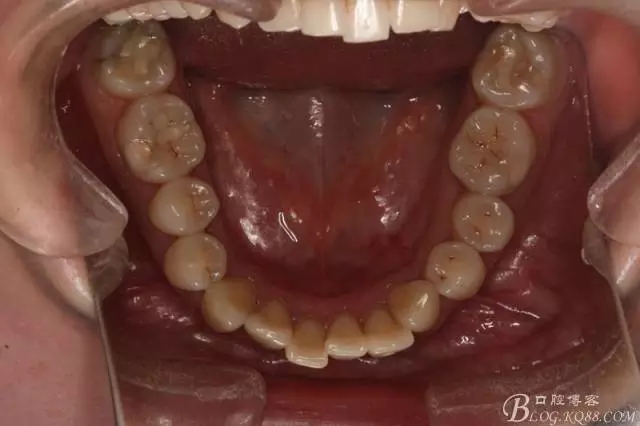

患者,女,主訴:牙齒不齊。

如圖,該病例為簡單排齊病例,但77鎖合是矯治中的關鍵所在,你會怎么處理?